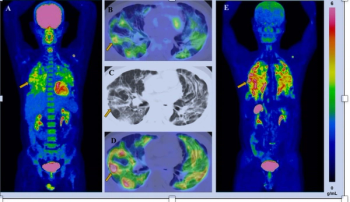

Multimodal treatment monitoring, including SPECT/CT exams 24 hours after treatment with Lu-177 PSMA-617, may have facilitated significantly shorter therapy durations and reduced side effects in patients with mCRPC, according to a two-year study presented at the Society for Nuclear Medicine and Molecular Imaging (SNMMI) conference.